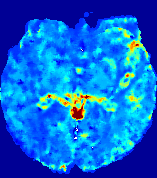

4.3.2 Diffusion Imaging via Advection-Diffusion

Slice #1Slice #2Slice #3Slice #4Slice #5Slice #6Dgtsuperscript𝐷gtD^{\text{gt}}Refer to captionRefer to captionRefer to captionRefer to captionRefer to captionRefer to captionDestsuperscript𝐷estD^{\text{est}}Refer to captionRefer to captionRefer to captionRefer to captionRefer to captionRefer to captionRefer to caption0.300.300.300.240.240.240.180.180.180.120.120.120.060.060.060.000.000.00(mm2/s)𝑚superscript𝑚2𝑠(mm^{2}/s)𝐕est𝟐subscriptnormsuperscript𝐕est2\|\bf{V}^{\text{est}}\|_{2}Refer to captionRefer to captionRefer to captionRefer to captionRefer to captionRefer to captionRefer to caption0.00300.00300.00300.00240.00240.00240.00180.00180.00180.00120.00120.00120.00060.00060.00060.00000.00000.0000(mm/s)𝑚𝑚𝑠(mm/s)

Figure 15: PIANO identifiability testing: diffusion imaging via advection-diffusion. Top row shows Dgtsuperscript𝐷gtD^{\text{gt}} used for simulating ground truth pure diffusion. Rows below show the estimated Destsuperscript𝐷estD^{\text{est}} and 𝐕est2subscriptnormsuperscript𝐕est2\|{\bf{V}}^{\text{est}}\|_{2} on corresponding slices. Note that the plotted value scale for 𝐕est2subscriptnormsuperscript𝐕est2\|{\bf{V}}^{\text{est}}\|_{2} is 0.01 of that for Dgtsuperscript𝐷gtD^{\text{gt}} and Destsuperscript𝐷estD^{\text{est}}.

Similarly, we test the behavior of PIANO when estimating both advection and diffusion from a pure diffusion-driven process. The goal is to determine if PIANO is able to recognize that there is only diffusion governing the given concentration time-series. We use the same ‘Diffusion Imaging’ data simulation of Sec. 4.2.1 as the concentration dataset, PIANO estimates both velocity 𝐕estsuperscript𝐕est{\bf{V}}^{\text{est}} and diffusivity Destsuperscript𝐷estD^{\text{est}}. Estimation results in Fig. 15 confirm PIANO’s identifiability again: the estimated 𝐕est2subscriptnormsuperscript𝐕est2\|{\bf{V}}^{\text{est}}\|_{2} is almost invisible compared to Destsuperscript𝐷estD^{\text{est}}, even plotted with a 1%percent11\% value range compared to that for Destsuperscript𝐷estD^{\text{est}}. On the other hand, Destsuperscript𝐷estD^{\text{est}} achieves comparable estimation performance as ‘Diffusion Imaging via Diffusion’ in which PIANO predicts Destsuperscript𝐷estD^{\text{est}} alone (shown in Fig. 13).